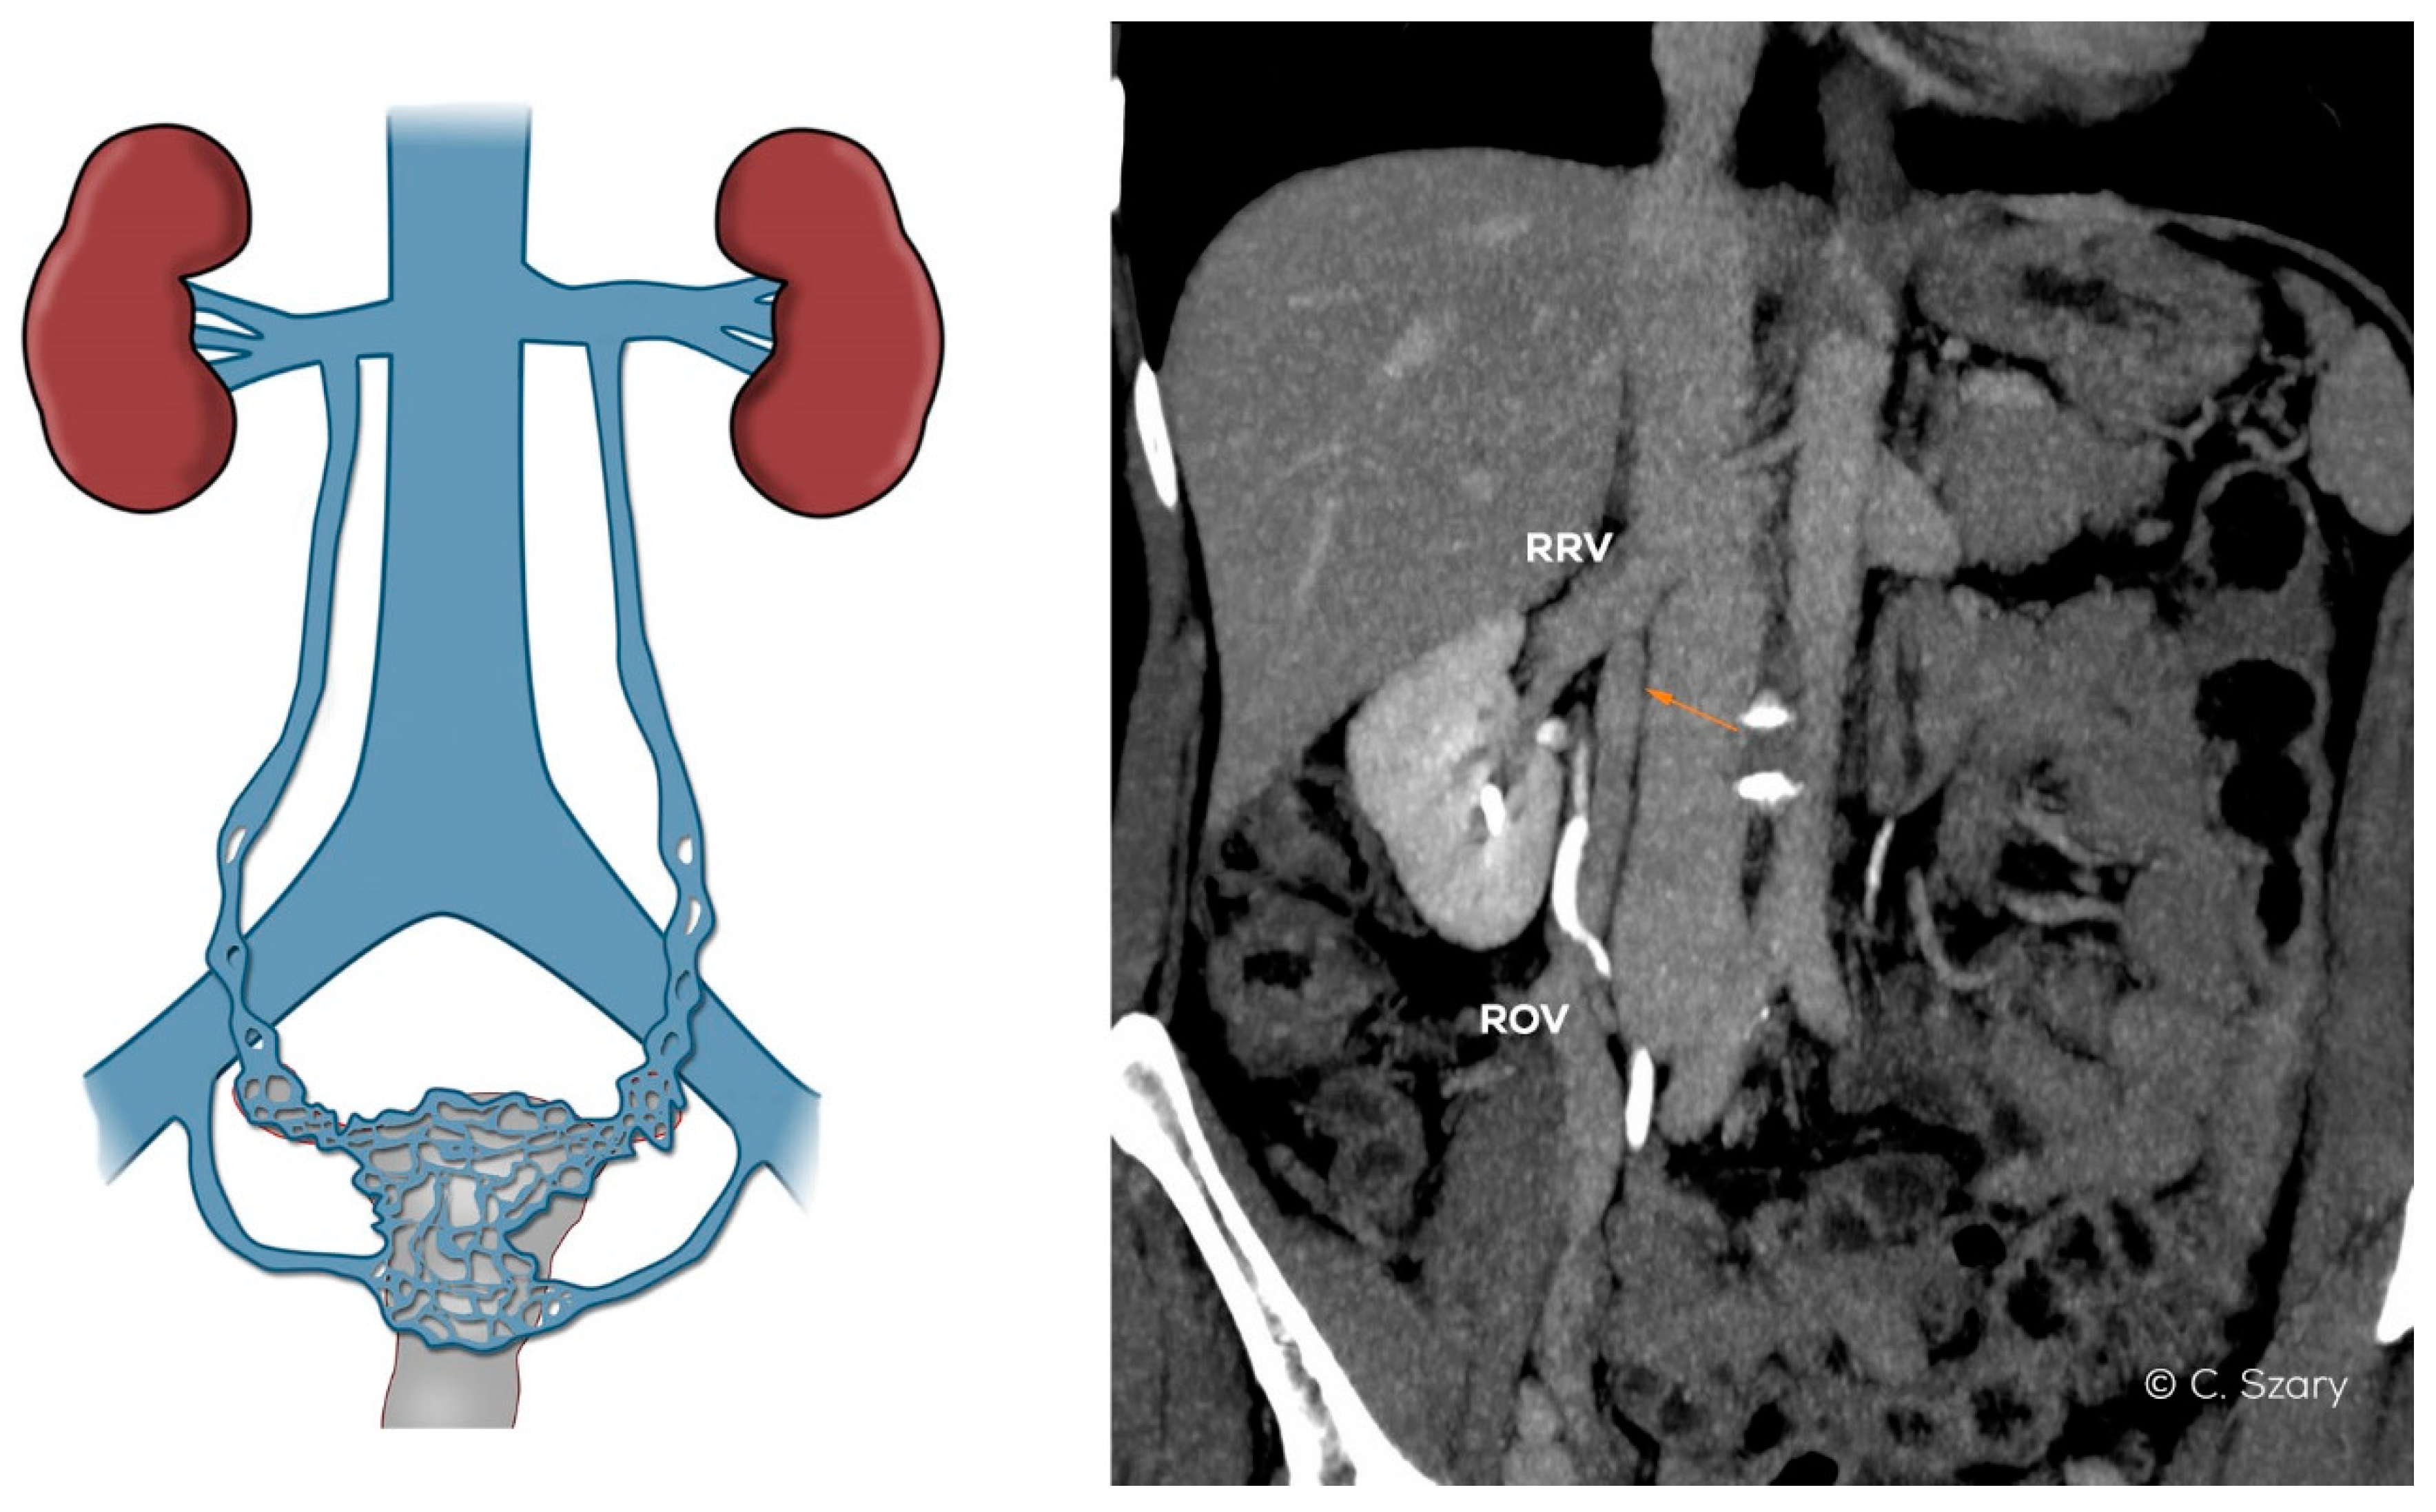

- atypical drainage of the right ovarian vein into the trunk of the right renal vein (Figure 7).

Figure 7. Atypical drainage of insufficient right ovarian vein (ROV) into right renal vein (RRV) on CTV image.